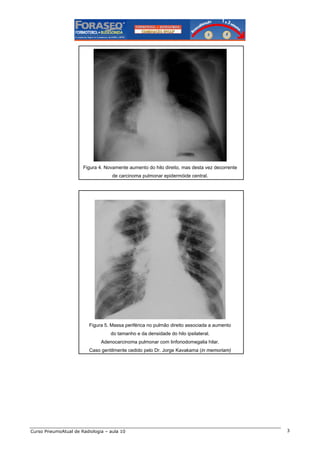

Figura 4. Novamente aumento do hilo direito, mas desta vez decorrente

de carcinoma pulmonar epidermóide central.

Figura 5. Massa periférica no pulmão direito associada a aumento

do tamanho e da densidade do hilo ipsilateral.

Adenocarcinoma pulmonar com linfonodomegalia hilar.

Caso gentilmente cedido pelo Dr. Jorge Kavakama (in memoriam)